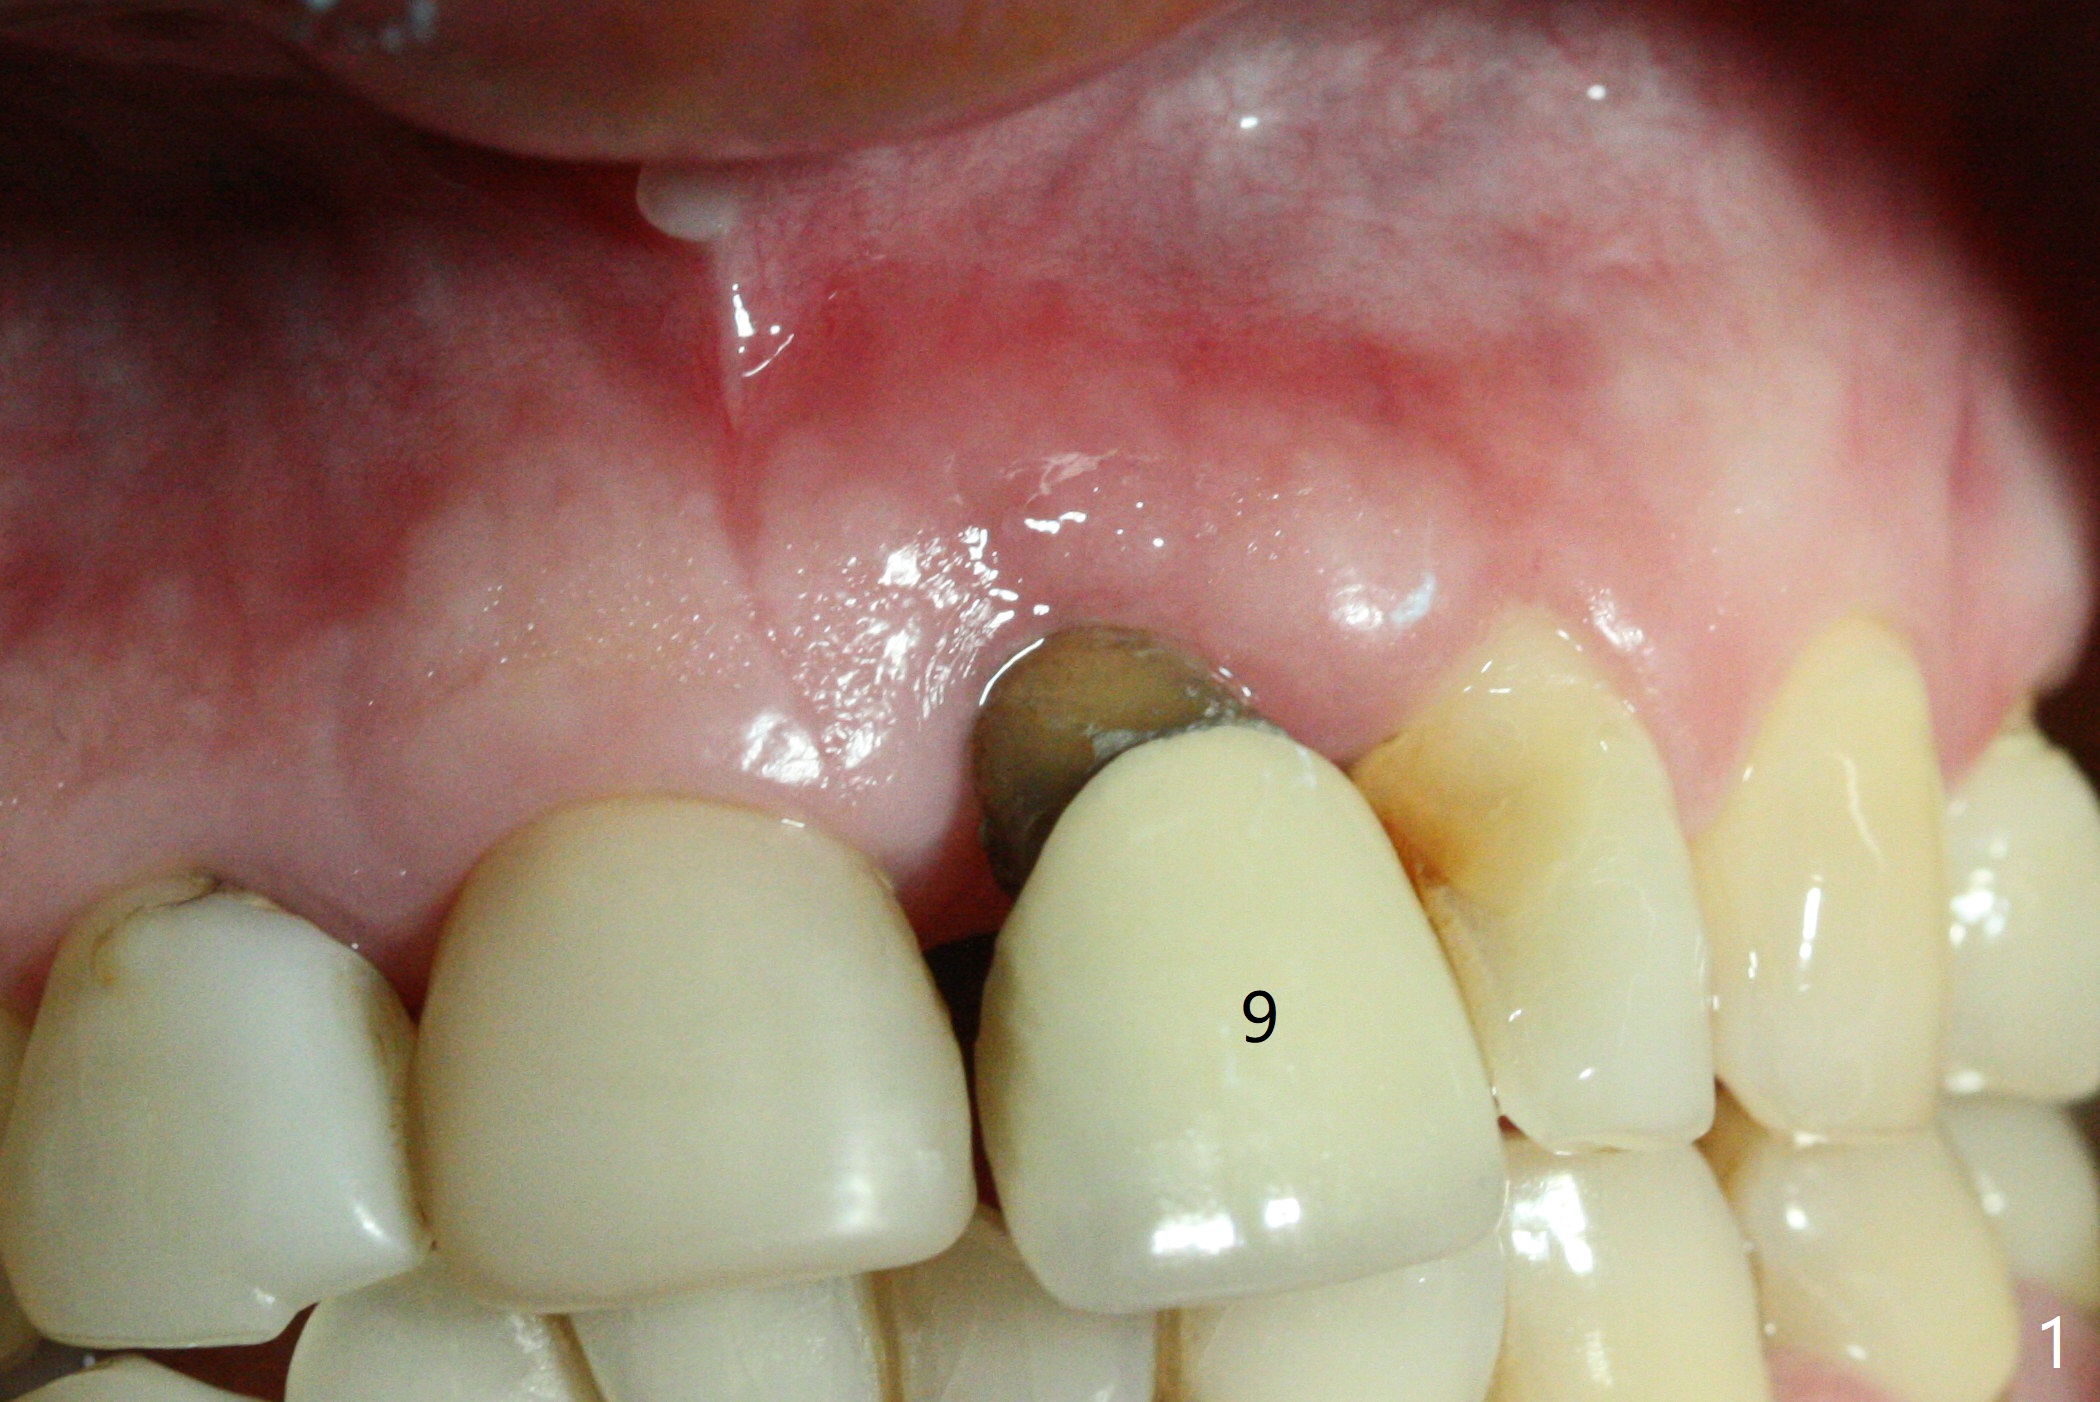

In spite of the incisobuccal shift of the tooth #9 with gingival recession (Fig.1) and loss of the buccal plate (intraop finding), there is no buccal contour collapse (Fig.2 *), due to the presence of the buccal bone of the neighboring teeth and the root of the affected tooth. After extraction, osteotomy (Fig.3) and dummy implant try in (Fig.4), a definitive implant is placed palatally with the buccal gap (Fig.5 *). In fact there is mild buccal contour collapse prior to bone graft (Fig.5 arrow). When allograft (Vera, Fig.6,7 *) is packed buccal to the implant and overlying abutment as a solid support, the buccal contour seemingly returns normal (Fig.6 arrowhead). An immediate provisional is fabricated to prevent loss of the bone graft during healing period. Bone graft kept in place by the provisional turns yellow 6 days postop (Fig.8). The buccal plate remains strong, while the fistula becomes indistinguishable. After adjustment of the provisional margin a few times (nearly 3 months postop, Fig.9,10), the gingival margin appears to have grown incisally, as compared to Fig.1. There is minimal buccal bone collapse (Fig.10). Dislodgement of the abutment and provisional forces her to return 1 year 4 months postop; the socket has healed (Fig.11). The buccal plate is not concave 1 year 4 months postop (Fig.12). The gingiva is slightly recessive (Fig.13) with mild buccal plate concavity (Fig.14) immediately before cementation. The implant could be placed ~ 1 mm deeper (Fig.15).